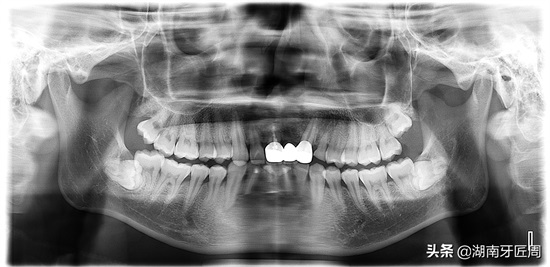

搜集平日里拍片常见的智齿图片,看看你的牙与下面几图相似。

图片3